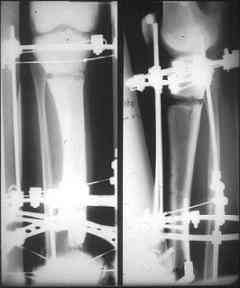

Может, данное наблюдение поможет в принятии решений в подобных ситуациях.

Огнестрельный дефект костей и передней группы мышц, поступил с юнилатеральным аппаратом, стабильность плохая, из раны обильное гнойное

отделяемое. #1;#2. Стержневой апп. снят, наложен апп. Илизарова, дренажно-ирригационная система промывки раны. #3; #4. После стихания инфекции,

аппаратом постепенно создана рекурвация для сближения контактов мышц (сухожилий) передней группы голени. #5;#6. Наложен шов на сухожлилия М.

Tibialis anterior и M extensor digitorum L. Одновременно компактотомия костей голени в В/3 для замешение дефекта костей. #7;#8. Постепенно

исправлена ось и возмещен дефект. В результате восстановление тыльной флекcии стопы и функции конечности. #9;#10;#11